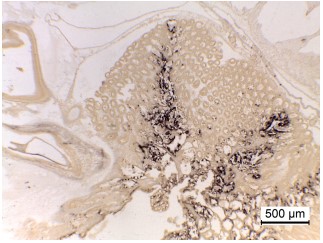

Hình 10. Hình ảnh với độ phóng đại thấp của mô HP bị nhiễm EHP từ xét nghiệm ISH với mẫu tôm con. Mẫu vật có tương đối ít tế bào đang tạo ra bào tử được xác định bằng phân tích mô học thông thường sử dụng nhuộm H&E thông thường. Mặc dù vậy, một tỷ lệ cao của ống các tế bào biểu mô ở khu vực trung tâm và trung gian của HP có thể được nhìn thấy là dương tính (nhuộm màu tối) cho thấy sự hiện diện của EHP, trong khi khu vực tế bào E xa vùng trung tâm cho kết quả nhuộm âm tính. Ngoài ra, sự phân bố của nhiễm các tế bào trong HP không đồng đều, do đó các mẫu nhỏ được lấy ngẫu nhiên từ các vùng của HP có thể cho kết quả PCR định lượng rất khác nhau đối với mức độ nghiêm trọng của nhiễm trùng EHP.